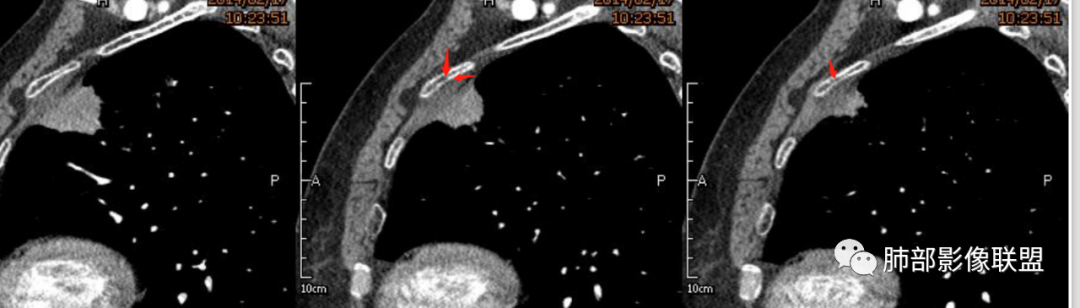

宽基底,附近胸膜增厚,边缘平直

支气管通畅

血管走形自然

坏死灶边界清附近卫星灶

意见:支持炎性。治疗后复查以排除恶性病变隐藏其中